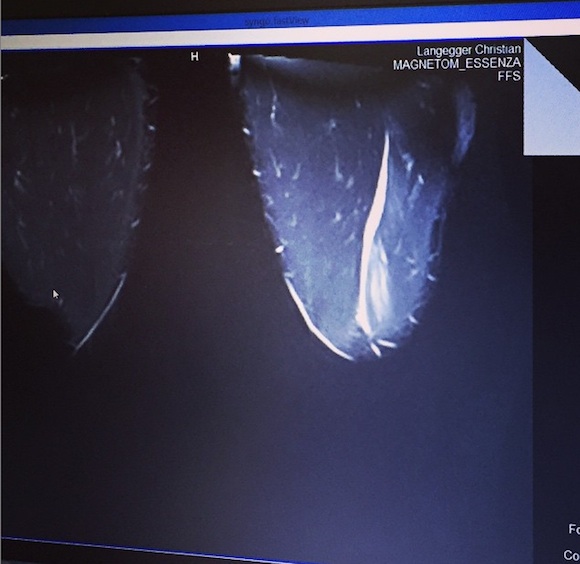

Георгиев публикува и рентгенова снимка, за да илюстрира каква точно е травмата му.